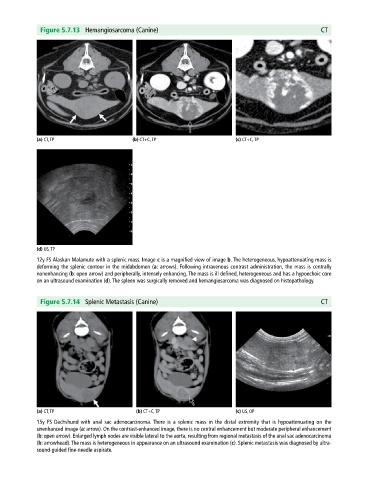

Figure 5.7.13 Hemangiosarcoma (Canine) CT

(a) CT, TP (b) CT+C, TP (c) CT+C, TP

(d) US, TP

12y FS Alaskan Malamute with a splenic mass. Image c is a magnified view of image b. The heterogeneous, hypoattenuating mass is

deforming the splenic contour in the midabdomen (a: arrows). Following intravenous contrast administration, the mass is centrally

nonenhancing (b: open arrow) and peripherally, intensely enhancing. The mass is ill defined, heterogeneous and has a hypoechoic core

on an ultrasound examination (d). The spleen was surgically removed and hemangiosarcoma was diagnosed on histopathology.

Figure 5.7.14 Splenic Metastasis (Canine) CT

(a) CT, TP (b) CT+C, TP (c) US, OP

15y FS Dachshund with anal sac adenocarcinoma. There is a splenic mass in the distal extremity that is hypoattenuating on the

unenhanced image (a: arrow). On the contrast‐enhanced image, there is no central enhancement but moderate peripheral enhancement

(b: open arrow). Enlarged lymph nodes are visible lateral to the aorta, resulting from regional metastasis of the anal sac adenocarcinoma

(b: arrowhead). The mass is heterogeneous in appearance on an ultrasound examination (c). Splenic metastasis was diagnosed by ultra

sound‐guided fine‐needle aspirate.